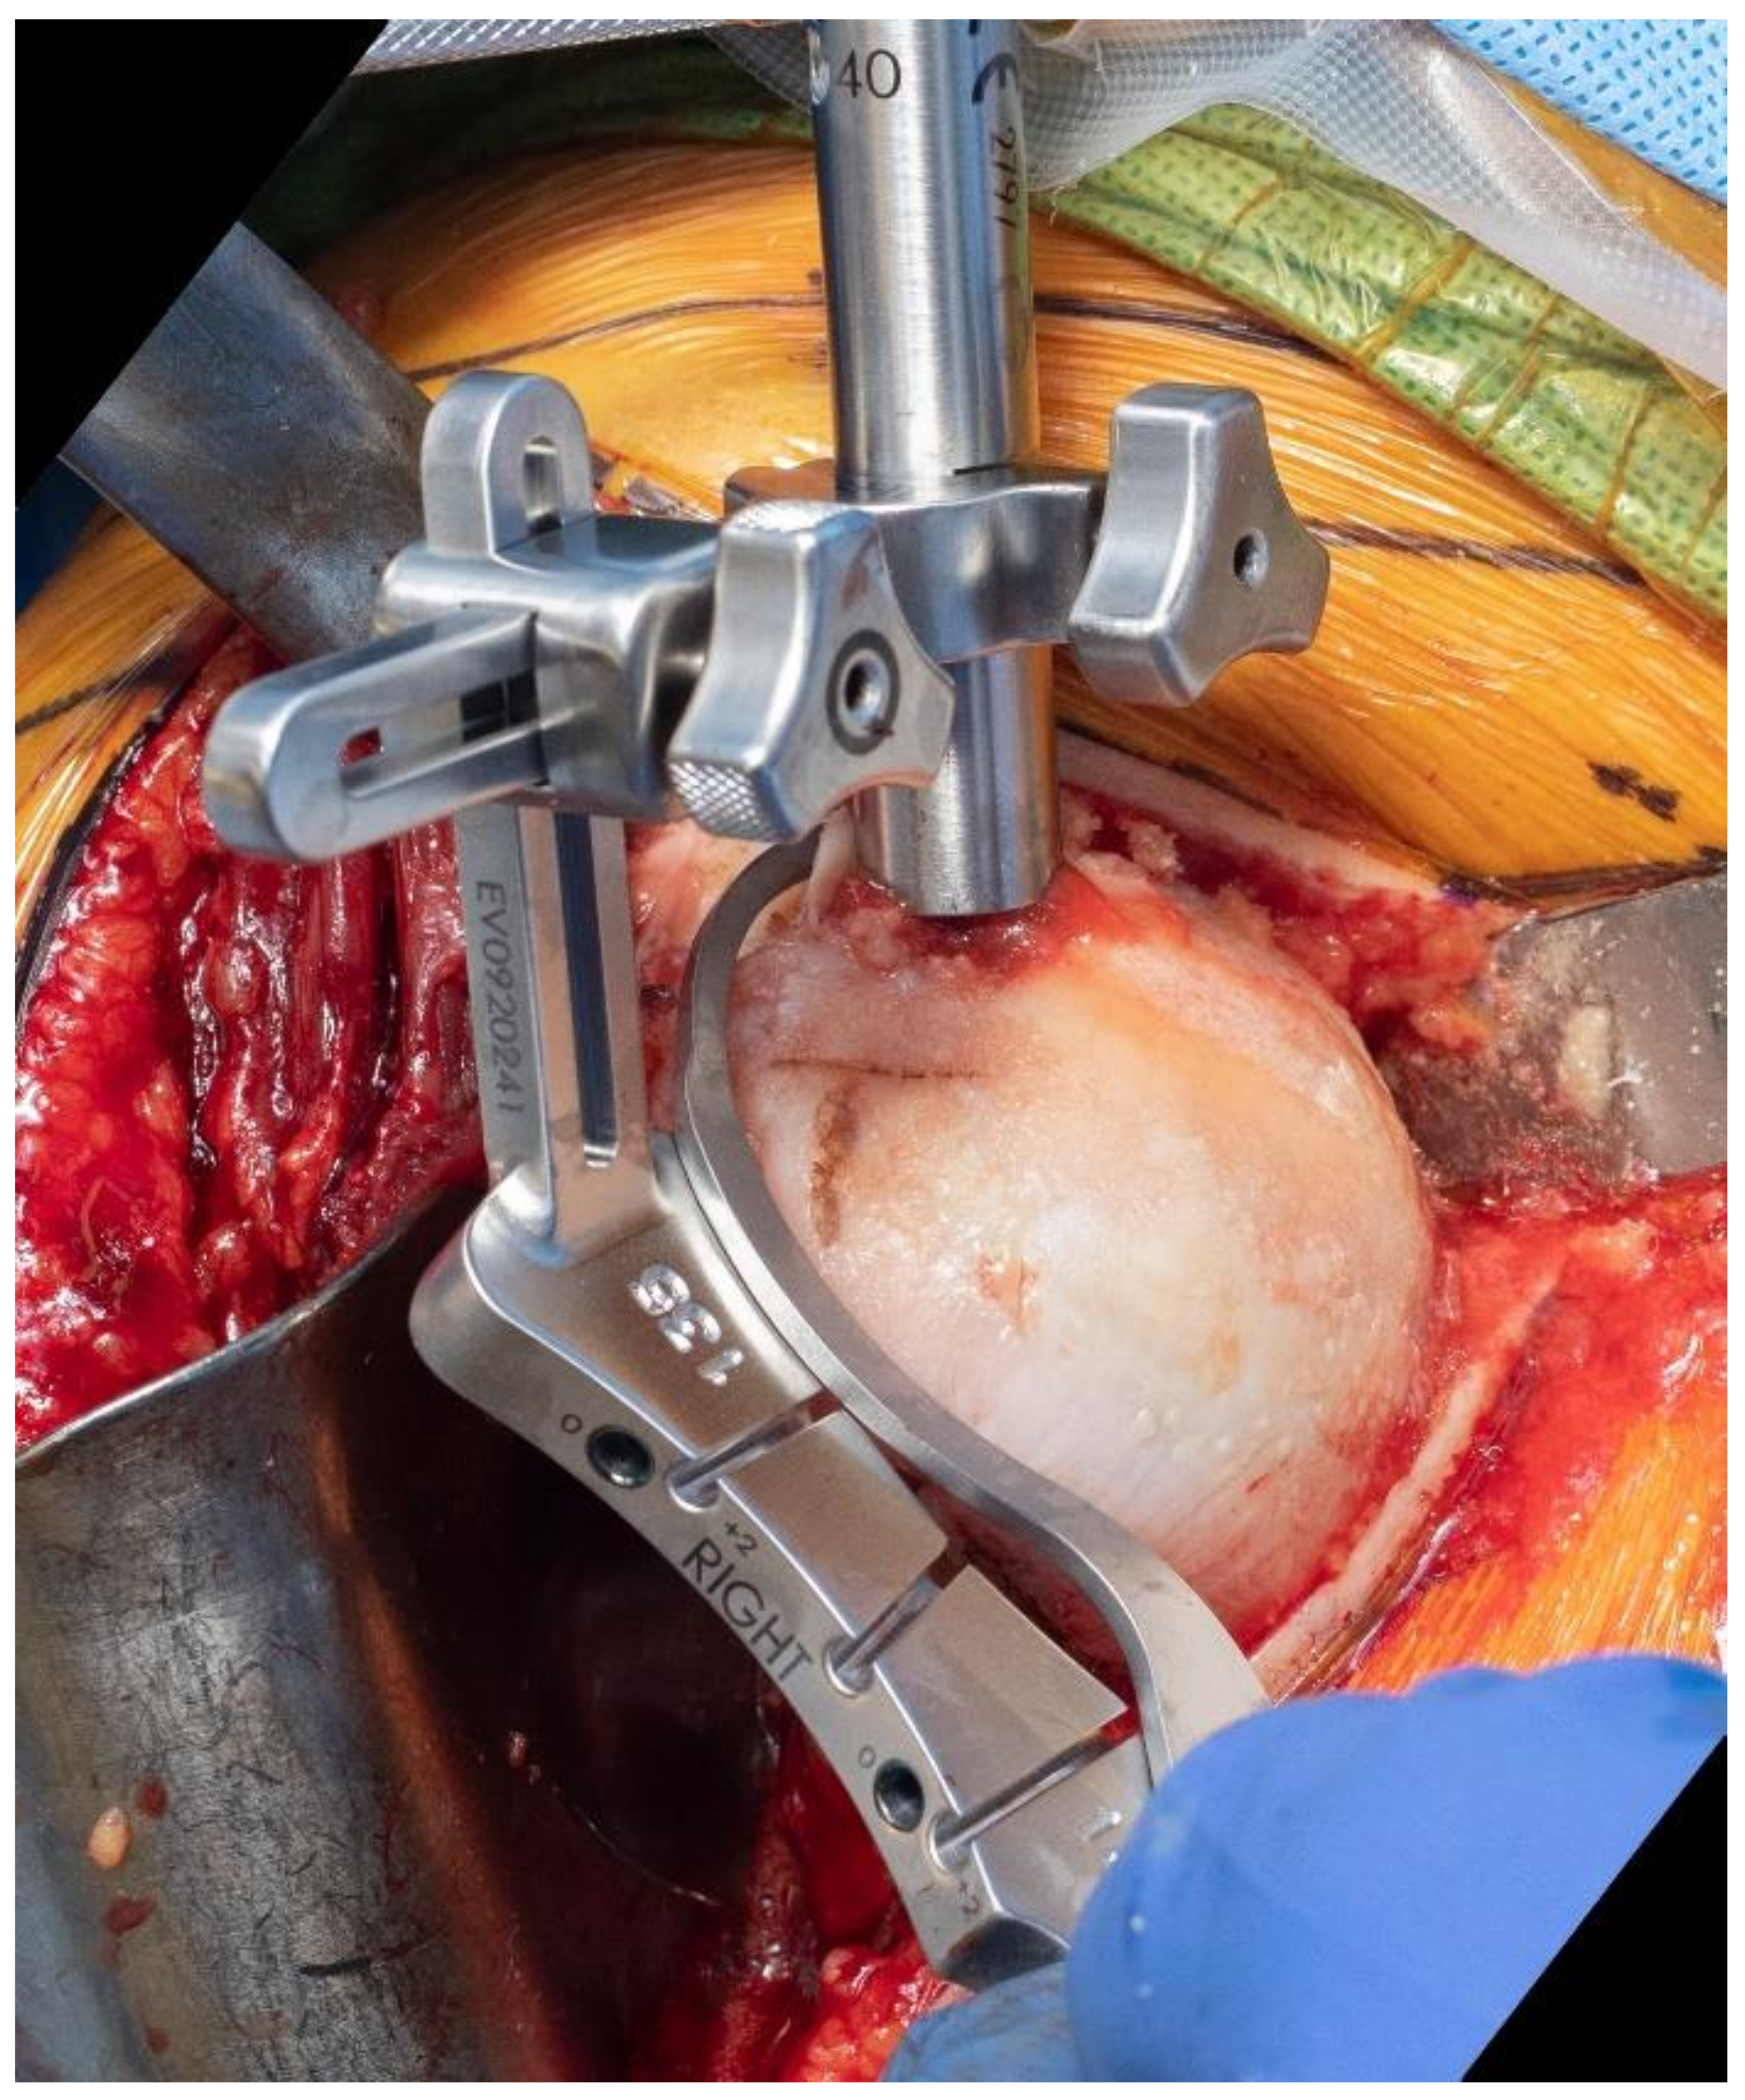

Many surgeons are used to performing the humeral head osteotomy with so-called freehand techniques. However, for those implants with a fixed neck–shaft angle, it may be advantageous to use an extramedullary or an intramedullary guide. Our preference is to use an intramedullary guide, and the selection of the entry point of the guide is paramount to avoid a varus or valgus cut. A C–guide may then be used to select the ideal cut height (Figure 7).

Figure 7.

Use of an extramedullary cutting guide may facilitate predictable osteotomy of the humerus in a specific degree of inclination.